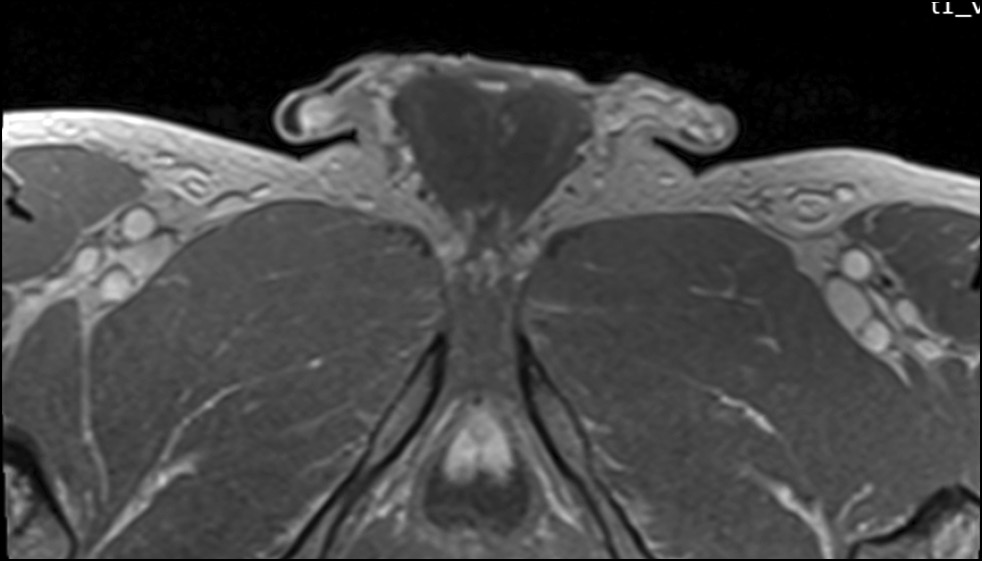

Рис. 4. Область ишемии левого яичка на аксиальном срезе (T2-взвешенное изображение).

Рис. 5. Область гипоинтенсивного сигнала на аксиальном срезе левого яичка на разных уровнях (в режиме с последовательностью инверсии-восстановления [Short Tau Inversion Recovery, STIR]).